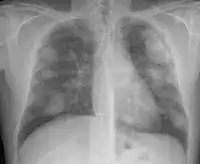

For uncomplicated silicosis, chest x-ray will confirm the presence of small (< 10 mm) nodules in the lungs, especially in the upper lung zones. Using the ILO classification system, these are of profusion 1/0 or greater and shape/size "p", "q", or "r". Lung zone involvement and profusion increases with disease progression. In advanced cases of silicosis, large opacity (> 1 cm) occurs from coalescence of small opacities, particularly in the upper lung zones. With retraction of the lung tissue, there is compensatory emphysema. Enlargement of the hilum is common with chronic and accelerated silicosis. In about 5–10% of cases, the nodes will calcify circumferentially, producing so-called "eggshell" calcification. This finding is not pathognomonic (diagnostic) of silicosis. In some cases, the pulmonary nodules may also become calcified.

Chest X-ray showing uncomplicated silicosis